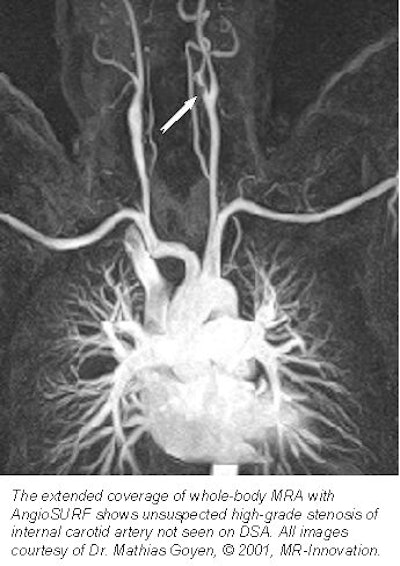

![]() |

"The extended anatomic coverage enabled the diagnosis of a high-grade stenosis of the internal carotid artery that wasn't known before, so we could provide the referring physician with some additional information," Goyen said. The procedure also correctly diagnosed 2 abdominal aortic aneurysms, 1 dissection, and 1 graft status, he said.

"The AngioSURF system allowed the accurate display of arteriovasculature from the supraaortic arteries to the lower extremity vessels," Goyen said. "Due to the extended coverage that's provided, we found additional findings that may be relevant to the treatment and diagnosis of vascular disease."